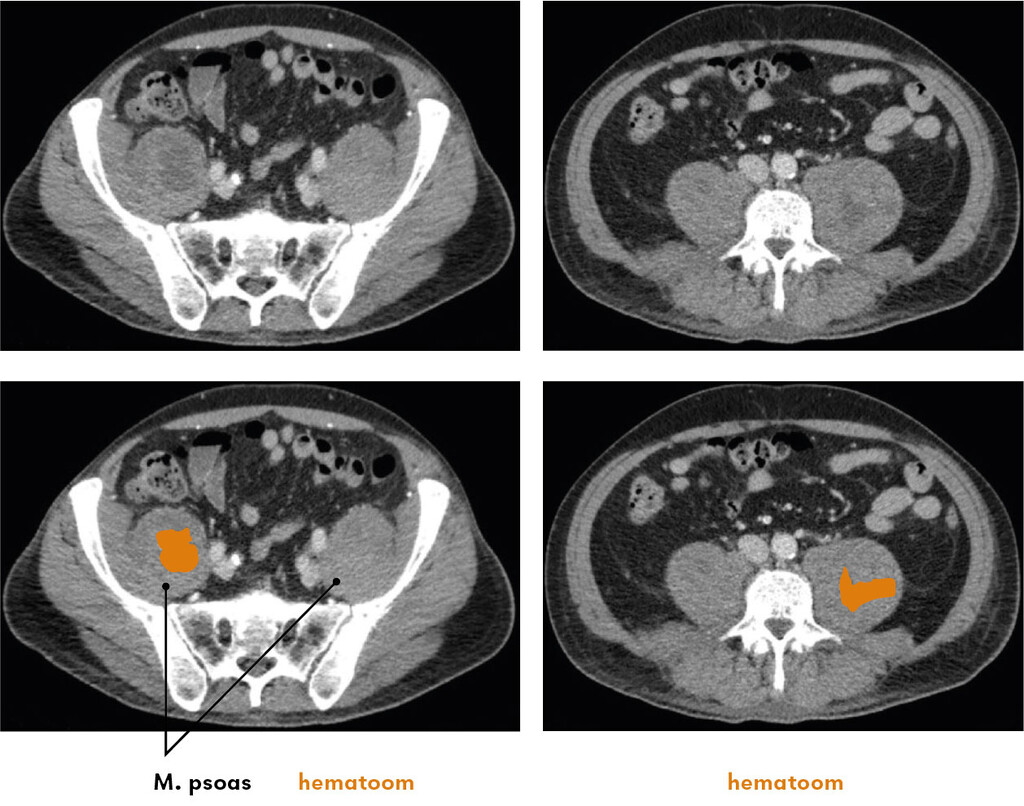

Figuur 2

CT-scans met contrast (transversale coupe) van een 66-jarige man met pijn in de onderbuik en liezen en spontane ecchymosen in de flanken. Hierop is bilateraal een iliopsoashematoom te zien zonder contrastextravasaat.

Op basis van het klinisch beeld en laboratoriumonderzoek dachten wij aan een bilateraal iliopsoashematoom. Een CT-scan met contrast bevestigde deze diagnose en sloot een actieve bloeding uit (figuur 2). De patiënt werd opgenomen en de fenprocoumon werd tijdelijk onderbroken maar niet gecoupeerd, vanwege de harde antistollingsindicatie en het ontbreken van een actieve bloeding.

Bilateraal iliopsoashematoom.